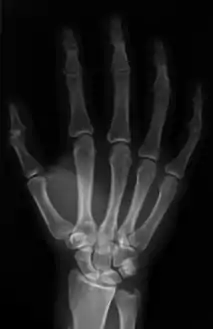

العظام

يد الإنسان مكونة من 27 عظاما :

- الرسغ ويضم 8 عظام تشكل صفين بكل واحد 4 عظام.

- مشط اليد وهو مجموعة العظام التي تشكل راحة اليد، وعددها 5.

- السلاميات هي مجموعة عظام أصابع اليد وعددها 14.